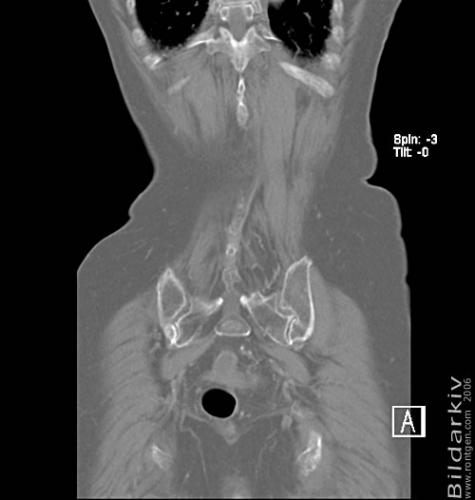

CT colon 44

Datortomografi av tjocktarmen (colon) med infunderad luft i tarmen samt med kontrast i blodbanan. Koronar bildserie.

CT multislice 16